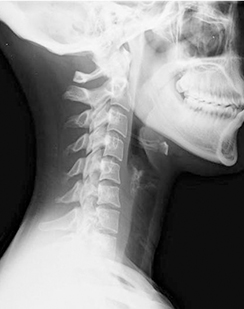

일자목 증후군

목뼈의 정상적인 전만(앞쪽으로 볼록함)이 소실되고 일자로 굳어지는 것입니다.

스마트폰과 컴퓨터 사용이 잦은 현대인에게 흔하며 목과 어깨에 통증이

발생하고, 두통이 생기기도 합니다.